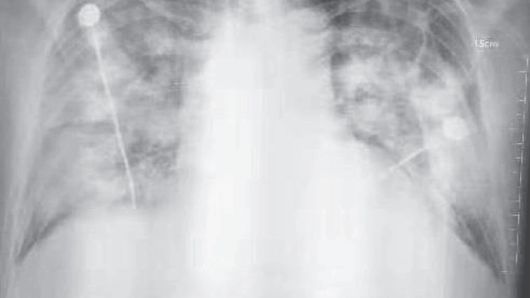

▲ 우한 폐렴 환자의 흉부 방사선 사진

AI가 검출할 수 있는 이상 소견은 ▲ 결절(폐에 생긴 작은 혹) ▲ 경화(폐 조직 일부가 딱딱하게 굳는 현상) ▲ 간질성 음영(폐 조직 사이의 공간에 이상이 생겨 X선 영상에서 비정상적으로 보이는 부분) ▲ 흉막삼출(폐를 둘러싼 막 사이 공간에 물이 차는 현상) ▲ 기흉(폐에 구멍이 생겨 공기가 새어 나오는 상태) 등 5가지 주요 질환입니다.

(사진=NEJM 논문 발췌, 연합뉴스)